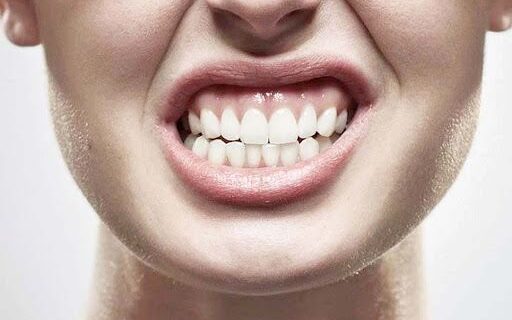

El bruxismo, o rechinamiento/apretamiento involuntario de los dientes, afecta a millones de personas en todo el mundo. En 2026, con el aumento del estrés digital y ritmos de vida acelerados, esta condición se ha convertido en una «epidemia silenciosa» que impacta no solo la salud dental, sino el bienestar general. Según metaanálisis recientes, aproximadamente el 25-26% de la población adulta sufre bruxismo, con cifras más altas en bruxismo diurno (23%) que nocturno (21%). En este artículo actualizado para 2026, exploramos las definiciones oficiales del Consenso Internacional sobre Bruxismo 2025, prevalencia real y por qué ya no se clasifica estrictamente como «trastorno» (al final te dejo el link directo a la publicación del Consenso).

Tipos principales de bruxismo:

- Bruxismo de vigilia (diurno): Apretamiento consciente o inconsciente durante el día, ligado a estrés, concentración o uso excesivo de pantallas.

- Bruxismo del sueño (nocturno): Ocurre durante el sueño, a menudo asociado a episodios de movimiento rítmico masticatorio (RMMA). Más destructivo por falta de control consciente.

SÍNTOMAS INICIALES DE BRUXISMO Y POR QUÉ ATENDERLO CUÁNTO ANTES

- Desgaste dental acelerado.

- Sensibilidad dental